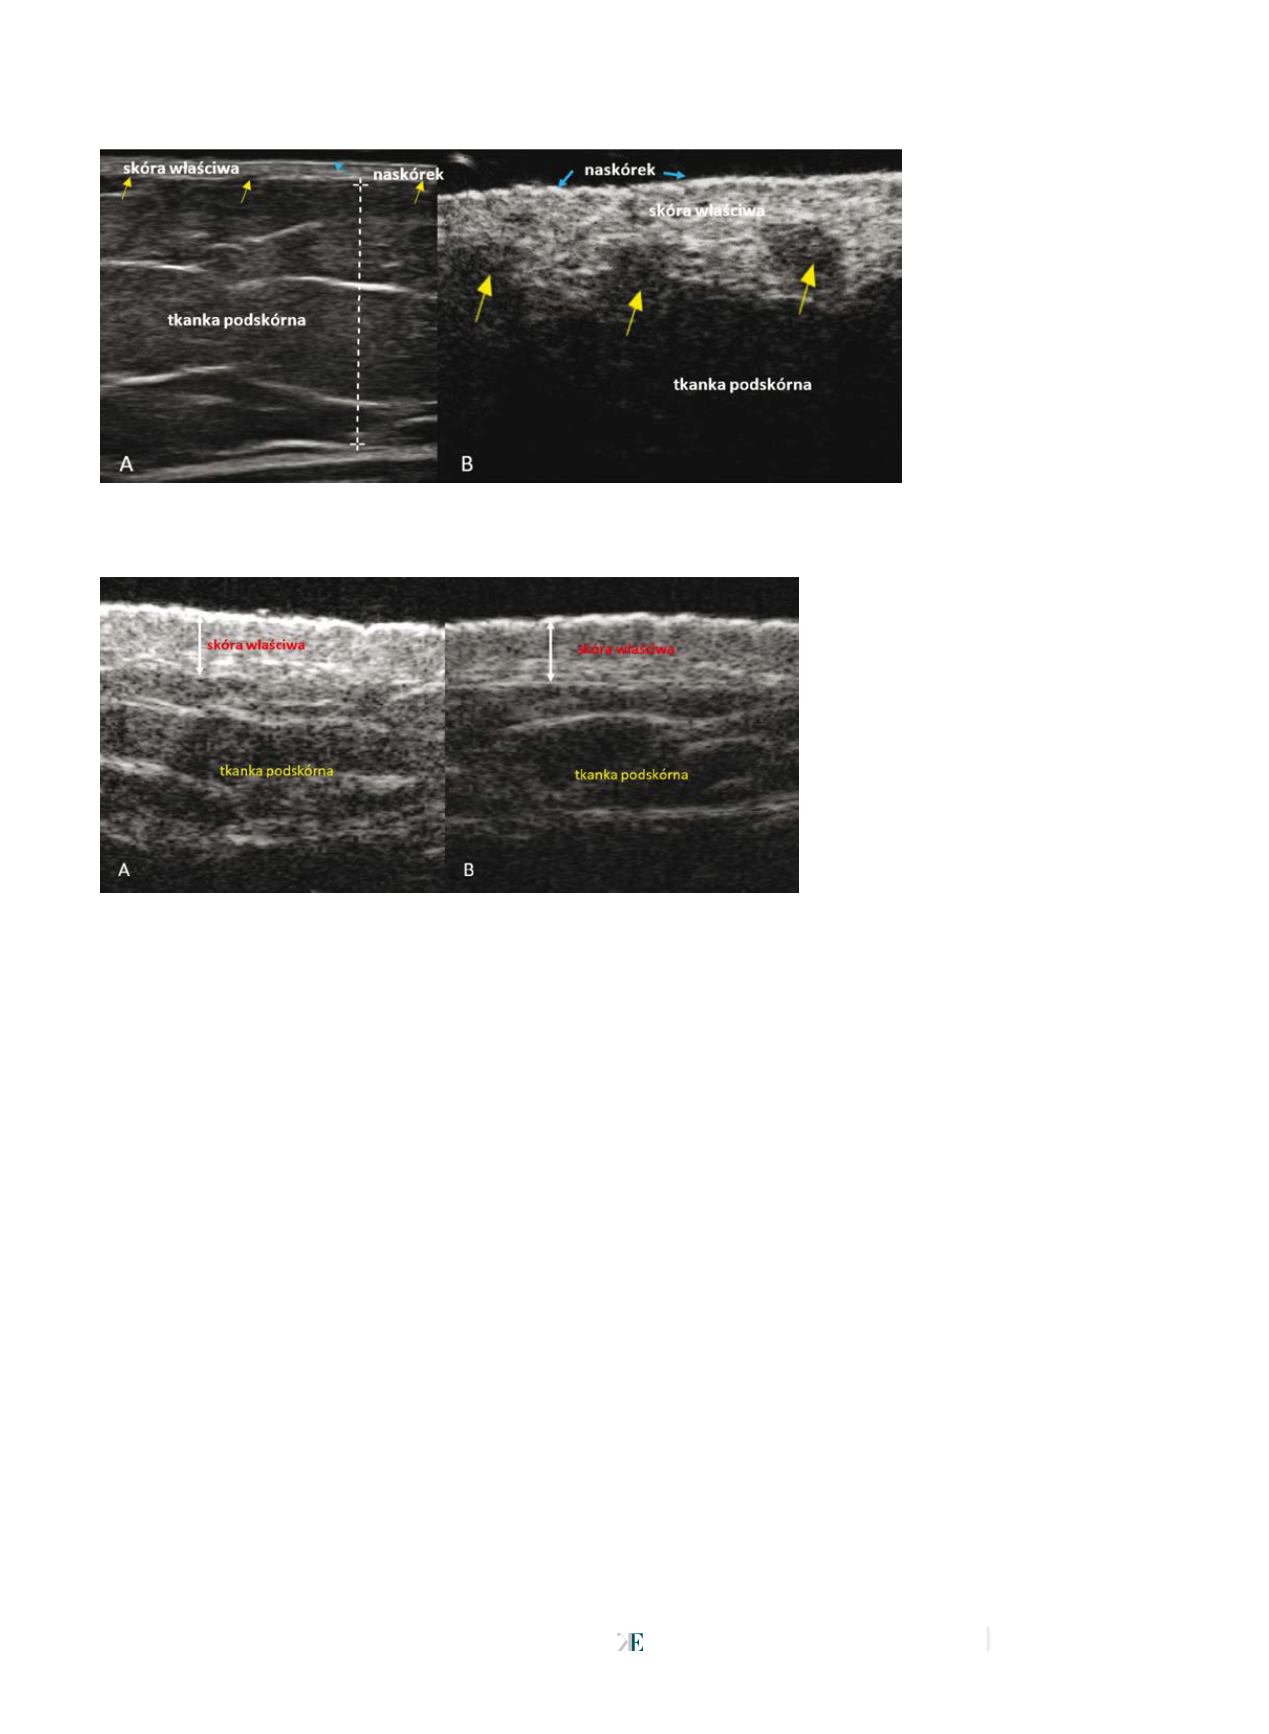

Fot. 3

Ultrasonograficzny obraz skóry przed zastosowaniem kosmetyków nawilżających (A) i po zakończeniu terapii (B).

Po terapii widoczny spadek echogeniczności skóry

Źródło:

Archiwum własne

W obrazowaniu ultrasonograficznym

wzrost nawilżenia skóry widoczny jest

jako zmiana echogeniczności [24]. We-

dług piśmiennictwa uchwytny wzrost

liczby pikseli może być obserwowany

już w drugim tygodniu od początku sto-

sowania substancji nawilżających [25].

Oceniając wpływ kosmetyków, prowa-

dzimy pomiary liczby pikseli w górnych

warstwach skóry, ponieważ wykazano,

że ten obszar skóry jest odpowiedzialny

za wiązanie wody [26] (fot. 3).